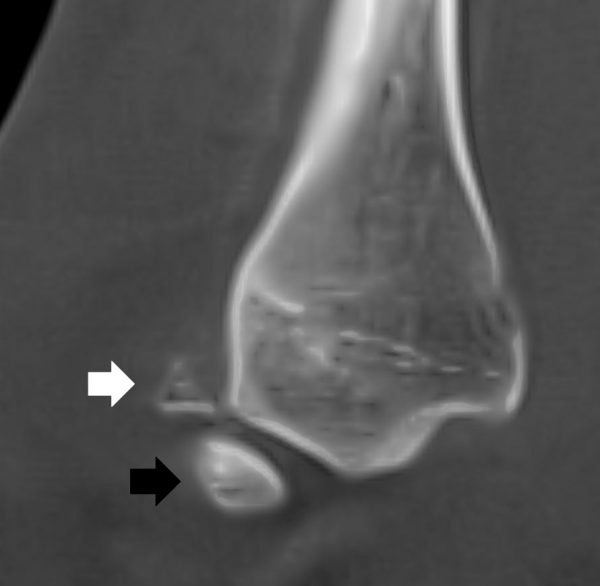

DVT & MRT als komplementäre Bildgebung

Wenn Begleitverletzungen vermutet werden oder der Befund klinisch nicht eindeutig ist, ergänzen sich DVT und MRT sinnvoll. Die DVT zeigt knöcherne Strukturen und gelenknahe Verletzungen besonders präzise. Das MRT ist wichtig für Bänder, Sehnen, Knorpel, Knochenmarkreaktionen und Weichteile. Beide Verfahren sind nicht alternativ, sondern komplementär.

- Zu Beginn nicht bemerkte Begleitverletzungen führen oft erst nach mehreren Wochen zu anhaltenden Beschwerden. Neben Verletzungen des Innenbandes und der Syndesmosenbänder sehen wir in unserer Praxis vor allem Durchblutungsstörungen des Sprungbeins – sogenannte Osteochondrale Läsionen des Talus (OCL), auch Osteochondrosis dissecans (OD) genannt. Dies sind schwerwiegende Verletzungsfolgen, die eine längerfristige Therapie und oft auch eine Operation erfordern. Daher ist es bei einem Umknickereignis besonders wichtig, gezielt nach solchen Begleitverletzungen des oberen Sprunggelenks zu suchen (MRT und DVT).